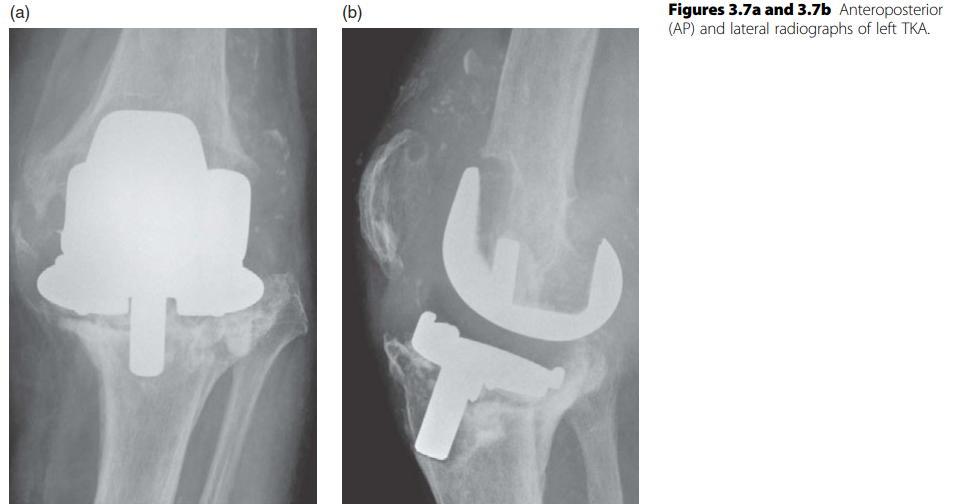

KNEE Structured oral examination question1: TKR in valgus knee EXAMINER : This is a radiograph of a 72-year-o…

KNEE Structured oral examination question7: Revision knee replacement EXAMINER : Have a look at these images …